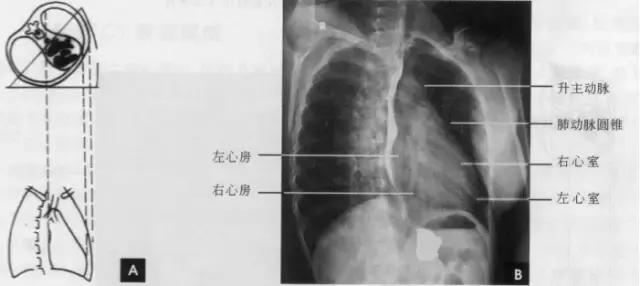

(右前斜位)

标准右前斜位(又称第一斜位)为后前位向左旋转约45。所得影像。心前缘自上而下由主动脉弓曼升主动脉、肺动脉、右心室漏斗部、右心室前壁和左心室下端构成。升主动脉前缘平直,弓部则在上方弯向后行;肺动脉段和漏斗部稍为隆起;心尖以上大部分为右心室构成。心前缘与胸壁之间有尖向下的三角形透明区称为心前间隙。心后缘上段为左心房,下段为右心房,两者无清楚分界。心后缘与脊柱之间透明区称心后间隙,食管在心后间隙通过,钡剂充盈时显影。右前斜位主要观察右室流出道及左心房大小(如下图)。

(三)左前斜位

从后前位向右旋转约60。得到左前斜位(又称第二斜位).此时室间隔与中心x线接*平近**行。因此.两个心室大致是对称的分为两半,前方一半为右心室.后方一半为左心室。心前缘上段为右心房.下段为右心室,右心房段主要由右心耳构成,房室分界不清。右心房影以上为升主动脉,两者相交成钝角:心后缘可分为上下两段,上段由左心房,下段则由左心室构成。左心室段的弧度较左心房大,两个不同弧度的交接点,可作为两者的分界。通过主动脉窗可兄气管分叉,主支气管和肺动脉,左主支气管下方为左心房影。左前斜位可了解各房室和主动脉情况(如下图)。

(四)左侧位

心影从后上向前下倾斜,心前缘下段为右心室前壁,上段则由右心室漏斗部与肺动脉主干构成,再苣上为升主动脉前壁,直向上走行。这些结构与翦髓壁之间的三角形透亮区称为胸骨后区。心后缘上中段由左心房构成,下段则由左心室构成。心后下缘、食管与膈之间的三角形间隙,为心后食管前间隙(如下图)。